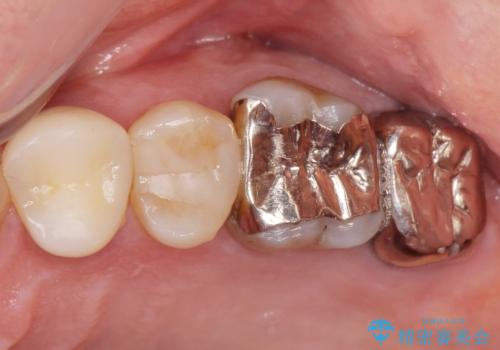

- 歯ぐき(ちょうど根の先のあたり)から膿が出て、根の治療を何度しても治らないことを主訴に来院された患者様です。

精査したところ、奥歯(左上67)の根尖部に位置した歯茎に瘻孔(膿の出口)ができており、CTを撮影し確認すると奥歯2本(左上67)の根尖病変は大きくつながっていました。

銀座しらゆり歯科の林院長による精密根管治療を受けて頂いたのち、メタルボンドクラウンによる補綴を行いました。